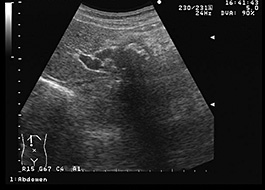

膵臓のエコー像 ここで、膵臓の代表的なエコー像とシェーマ像をそれぞれ2点ずつ紹介します(図2、図3)。 図2 膵臓のエコー像とシェーマ像(1) 膵臓の曲がっている形が映っていて、中の濃い部分は脾静脈です。 図3 膵臓のエコー像とシェーマ像(2). 肝の内部エコーは粗ぞうになっており、 門脈には腫瘍塞栓がみられる。 辺縁不整な 高エコーの腫瘍 大腸癌肝転移 輪郭が不明瞭で内部に微細な点状の 強エコー(石灰化)が散在している。 右腎 ここにも腫瘍? 明瞭な低エコー 明瞭な低エコー ここにも腫瘍? 乳癌肝転移 1cm径程度の低エコー. では、 犬の急性膵炎 とはどんな病気なのでしょうか? 超簡単かつ,アバウトな説明になりますが・・・ 膵臓とは、血糖値を上げたり、下げたりするホルモン(グルカゴンとインスリン)を分泌する臓器なのは有名ですね!.

1日目は3時間半かけて猫の肝臓、腎臓、膀胱、胃腸、膵臓、副腎などの超音波診断についてセミナーを聴講しました。 2日目は実際にねこちゃんのお腹に超音波をあてました。 わんちゃんもねこちゃんも腹腔内には以下のように様々な臓器があります。 私は病気や健康診断、中高齢の子の麻酔前. 30/05/19急性膵炎の犬26頭を用いた本研究では、 ct造影検査のほうが、膵臓全体の描出や膵臓腫大の判断 において優れていることが示されているが、一方で 腹水や腸間膜の異常などは超音波検査のほうが検出率が高く 、必ずしもすべてでct造影検査が優れているわけではないことがわかる。. 犬=膵臓 と一部腸粘膜 壊死や膿瘍→低エコー 性 辺縁の不整と高エコー性 膵壊死と膵腺癌は鑑別不可能 欠点 胃内および十二指腸内のガス貯留 重度の腹痛があると,評価が非常に困難 利点 膵臓の病変を容易に描出可能な症例では 針生検や膵嚢胞,膵偽嚢胞内の貯留液の吸引が可能.